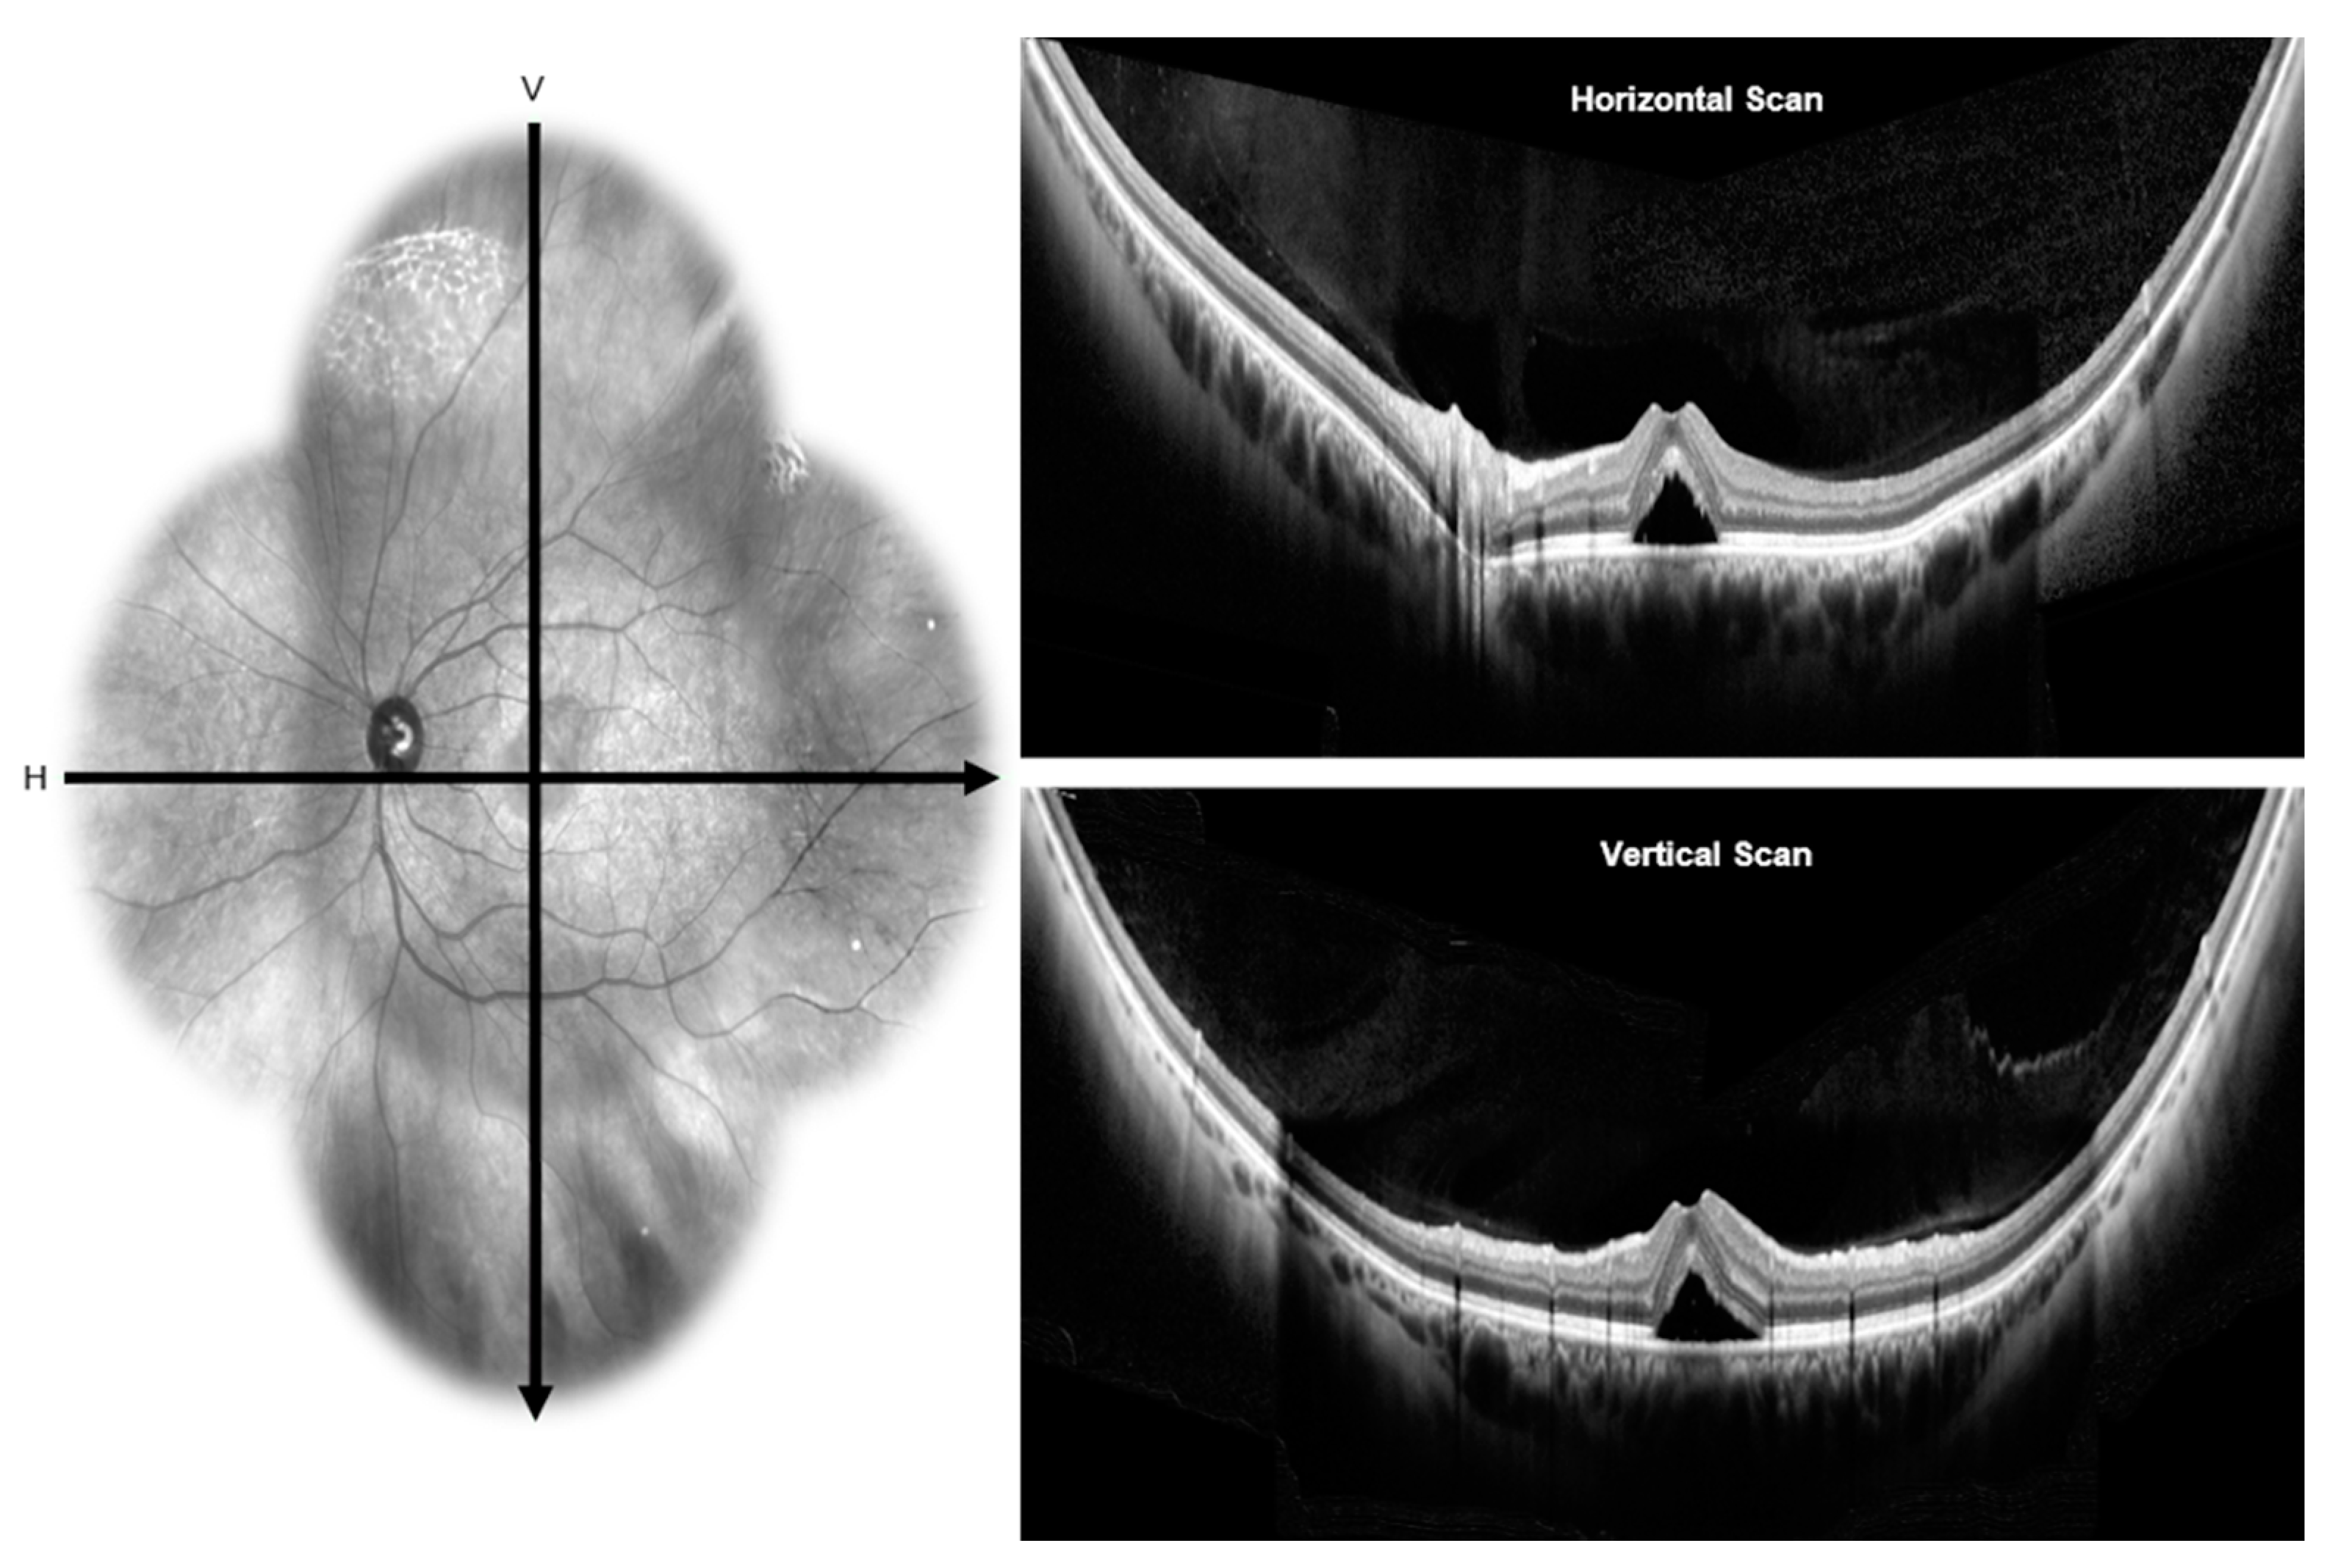

3.3. Wide Field Choroidal Vascularity and Choroidal Thickness in Healthy and CSCR

- Carrai, P.; Pichi, F.; Bonsignore, F.; Ciardella, A.P.; Nucci, P. Wide-field spectral domain-optical coherence tomography in central serous chorioretinopathy. Int. Ophthalmol. 2015, 35, 167–171. [Google Scholar] [CrossRef]